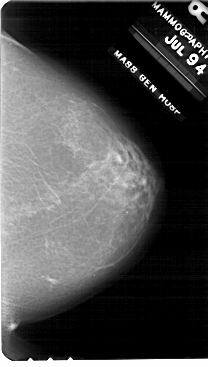

A_1707_1.LEFT_MLO

LEFT_MLO LINES 5491 PIXELS_PER_LINE 3856 BITS_PER_PIXEL 12 RESOLUTION 43.5 OVERLAY